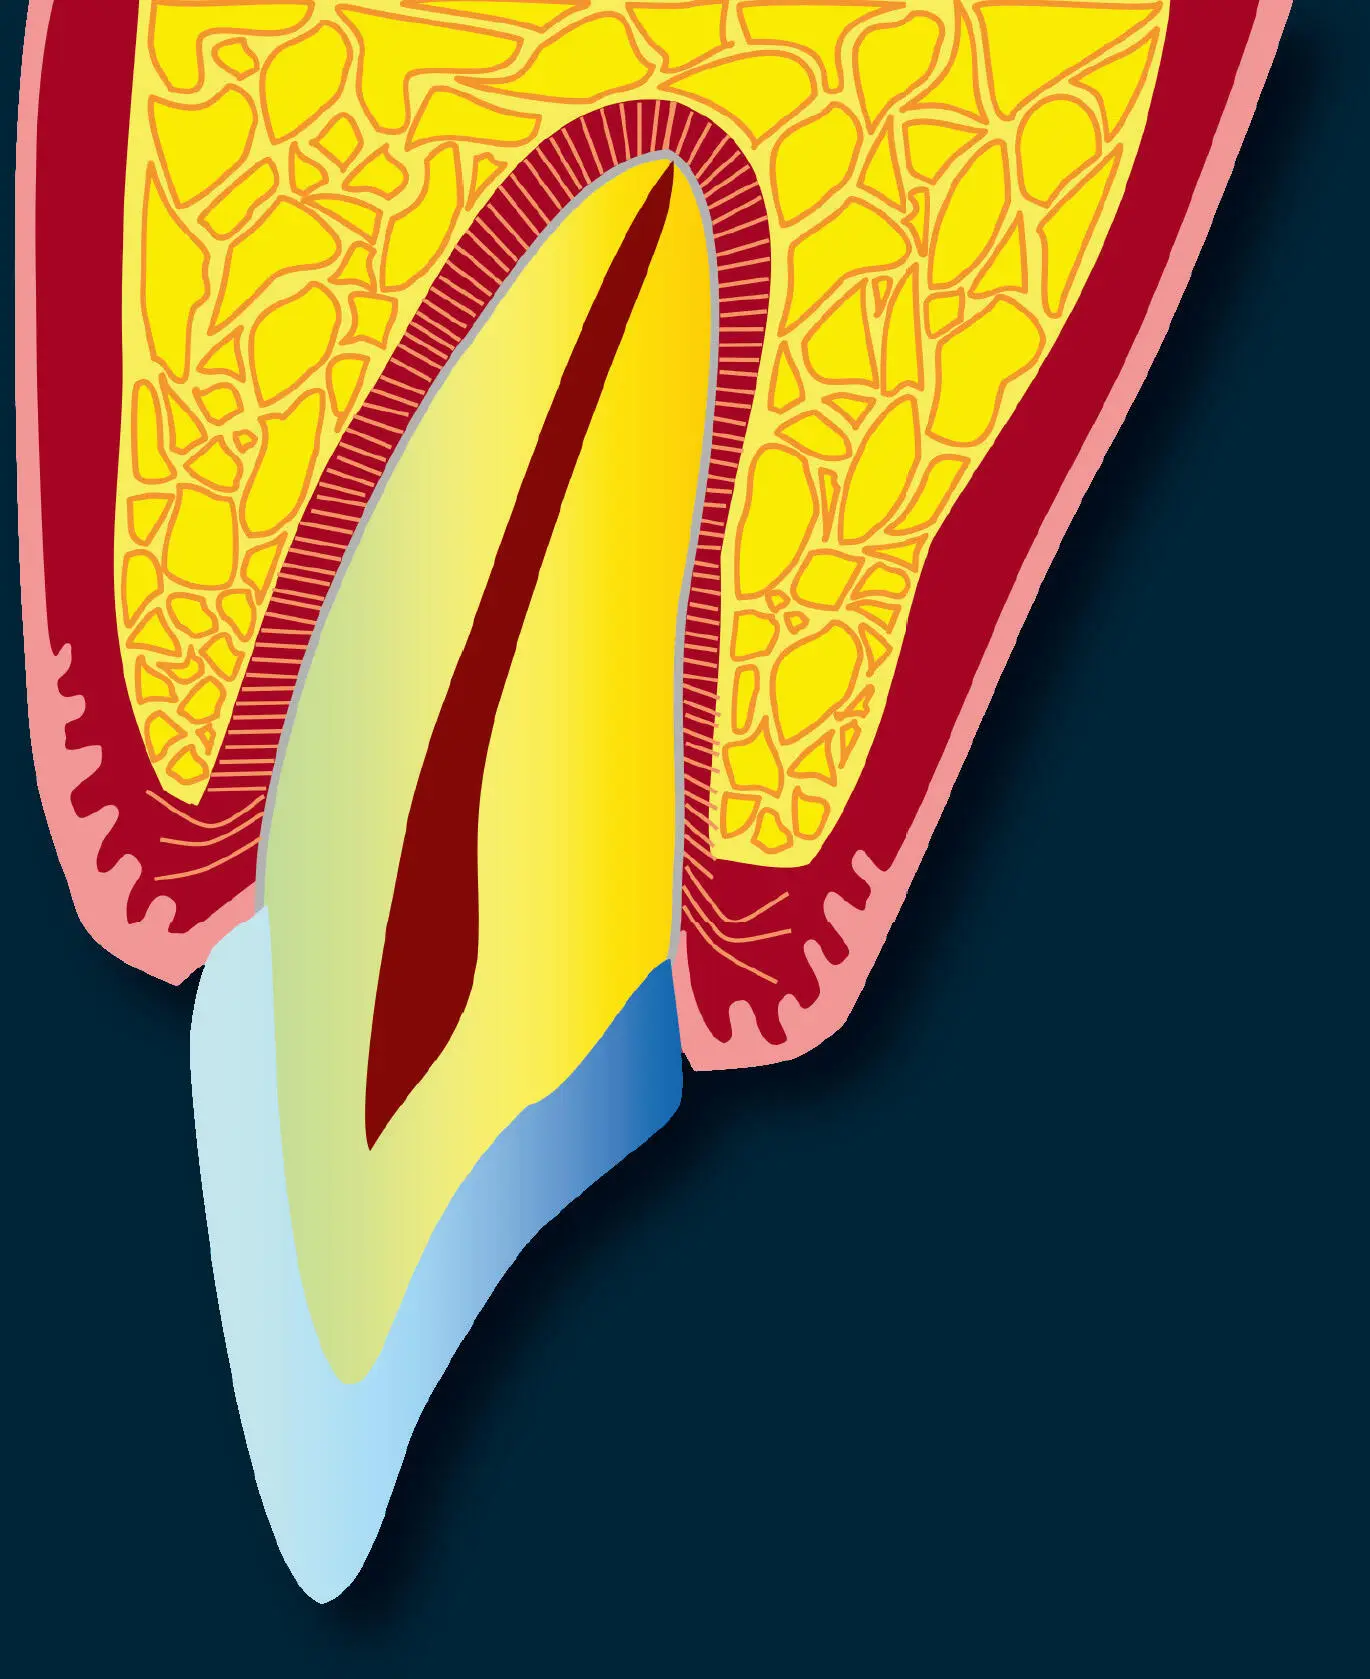

Die Zähne als solche bestehen zum einen aus Schmelz und Dentin und zum anderen aus dem das Pulpakavum ausfüllenden Pulpagewebe. Obwohl das Wurzelzement innig mit dem Dentin und z. T. der Schmelzoberfläche verbunden ist, stellt es definitionsgemäß einen Teil des Parodonts dar. Der Zahnhalteapparat, das Parodont, besteht aus vier Geweben: der Gingiva, dem Desmodont, dem Wurzelzement und dem Alveolarknochen. Der letztere besteht aus dem eigentlichen Alveolarknochen, der mit der Lamina cribriformis der Alveole gleichzusetzen ist, und dem Alveolarfortsatz ( Abb. 1). Desmodont, Wurzelzement und eigentlicher Alveolarknochen entstammen als ektomesenchymale Gewebe dem Zahnsäckchen. Herkunftsmäßig ist Epithelgewebe uneinheitlich, da alle embryonalen Keimblätter in der Lage sind, Epithelgewebe zu bilden. Das Epithel der Mundschleimhaut ist zum Teil ektodermaler (Lippen, Vestibulum, Gingiva, Wangen, Gaumen, Mundboden) und zum Teil entodermaler (Zunge) Herkunft. Das Parodont verfügt über Rezeptoren, die Schmerz, taktile Reize und Druck übertragen. Die Funktion des Parodonts besteht zum einen darin, den Zahn im Kiefer zu verankern und zum anderen das aseptische Ökosystem der inneren Gewebe von der bakteriell kontaminierten Mundhöhle abzuschirmen 1,2.

Abb. 1 Das Parodont als funktionelle Einheit besteht aus vier Geweben: der Gingiva propria, dem Desmodont, dem Wurzelzement und dem eigentlichen Alveolarknochen, der mit der Lamina cribriformis der Alveole gleichzusetzen ist.